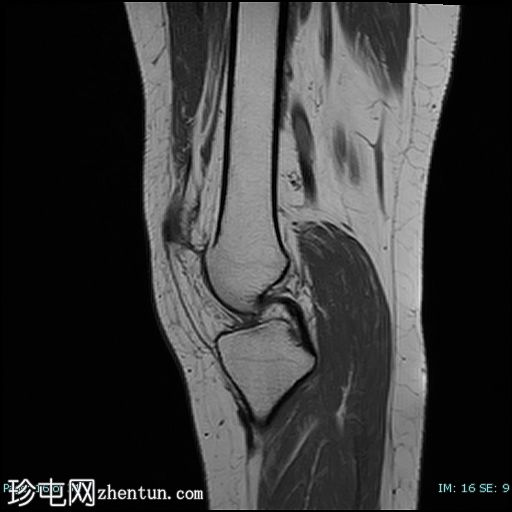

轴位

T2加权像

9.png